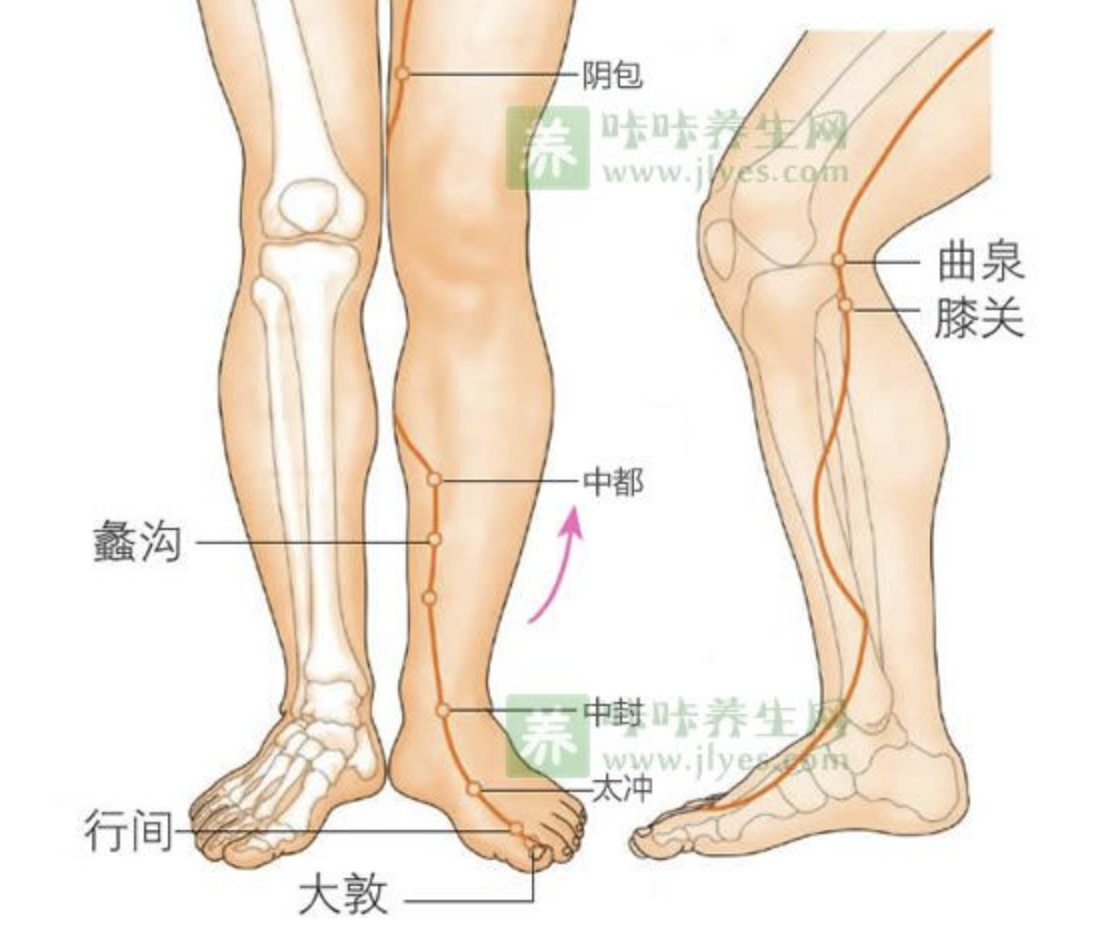

曲泉

【定位】 在膝内侧,屈膝,当膝关节内侧端,股骨内侧髁的后缘,半腱肌、半膜肌止端的前缘凹陷处。

【主治】 月经不调,痛经,带下,阴挺,阴痒,产后腹痛,遗精,阳痿,疝气,小便不利,头痛,目眩,癫狂,膝髌肿痛,下肢痿痹。

【配伍】 配丘墟、阳陵泉治胆道疾患,配肝俞、肾俞、章门、商丘、太冲治肝炎,配复溜、肾俞、肝俞治肝肾阴虚之眩晕,翳障眼病,配支沟、阳陵泉治心腹疼痛、乳房胀痛、疝痛,配归来、三阴交治肝郁气滞之痛经、月经不调。

【刺灸法】 直刺 1 ~ 1.5 寸;可灸。

【附注】 肝经合穴。

章门

【定位】 在侧腹部,当第 11 肋游离端的下方(图 10-30-2)。

【主治】 腹痛,腹胀,肠鸣,泄泻,呕吐,神疲肢倦,黄疸,痞块,小儿疳积,腰脊痛。

【配伍】 配足三里治荨麻疹、组织胺过敏症,配天枢、脾俞、中脘、足三里治肝脾不和之腹胀、痞块、胁痛,泄泻,消瘦,配肾俞、肝俞、水道、京门、阴陵泉、三阴交、阳谷、气海治肝硬化腹水、肾炎。

【刺灸法】 斜刺 0.5 ~ 0.8 寸;可灸。

【附注】 脾的募穴,八会穴之脏会。

期门

【定位】 在胸部,当乳头直下,第 6 肋间隙,前正中线旁开 4 寸(图 10-30-2)。

【主治】 胸胁胀满疼痛,呕吐,呃逆,吞酸,腹胀,泄泻,饥不欲食,胸中热,咳喘,奔豚,疟疾,伤寒热入血室。

【配伍】 配大敦治疝气,配肝俞、公孙、中脘、太冲、内关治肝胆疾患、胆囊炎、胆结石及肝气郁结之胁痛、食少、乳少、胃痛、呕吐、呃逆、食不化、泄泻等。

【刺灸法】 斜刺 0.5 ~ 0.8 寸;可灸。

【附注】 肝的募穴。